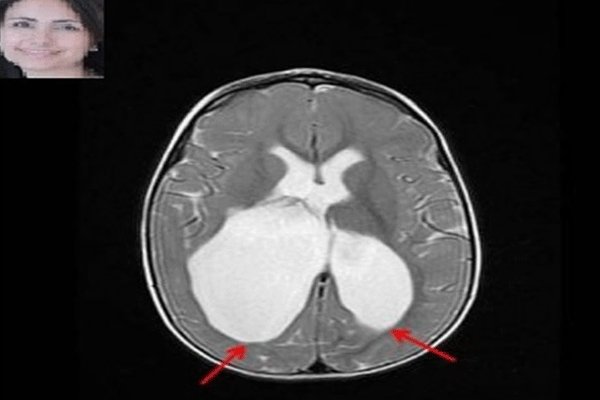

محققان کانادایی به سرپرستی دکتر «مریم اسکویی»، متخصص مغز و اعصاب بیمارستان کودکان مونترال کانادا موفق به کشف عامل ژنتیکی فلج مغزی شدند.

مطالعات محققان نشان می دهد، مولفه های ژنتیکی در بروز فلج مغزی بیش از تصورات پیشین نقش دارند. در این مطالعه به چگونگی تعامل عوامل خطر ژنتیکی نیز پرداخته شده است.

نتایج این مطالعه می تواند باورهای گذشته درباره عوامل فلج مغزی را تغییر دهد زیرا پیش از این تصور می شد عفونت و خفگی هنگام تولد عاملی برای فلج مغزی هستند، به همین دلیل توجهی به آزمایشات ژنتیکی پیش از بارداری نمی شد.